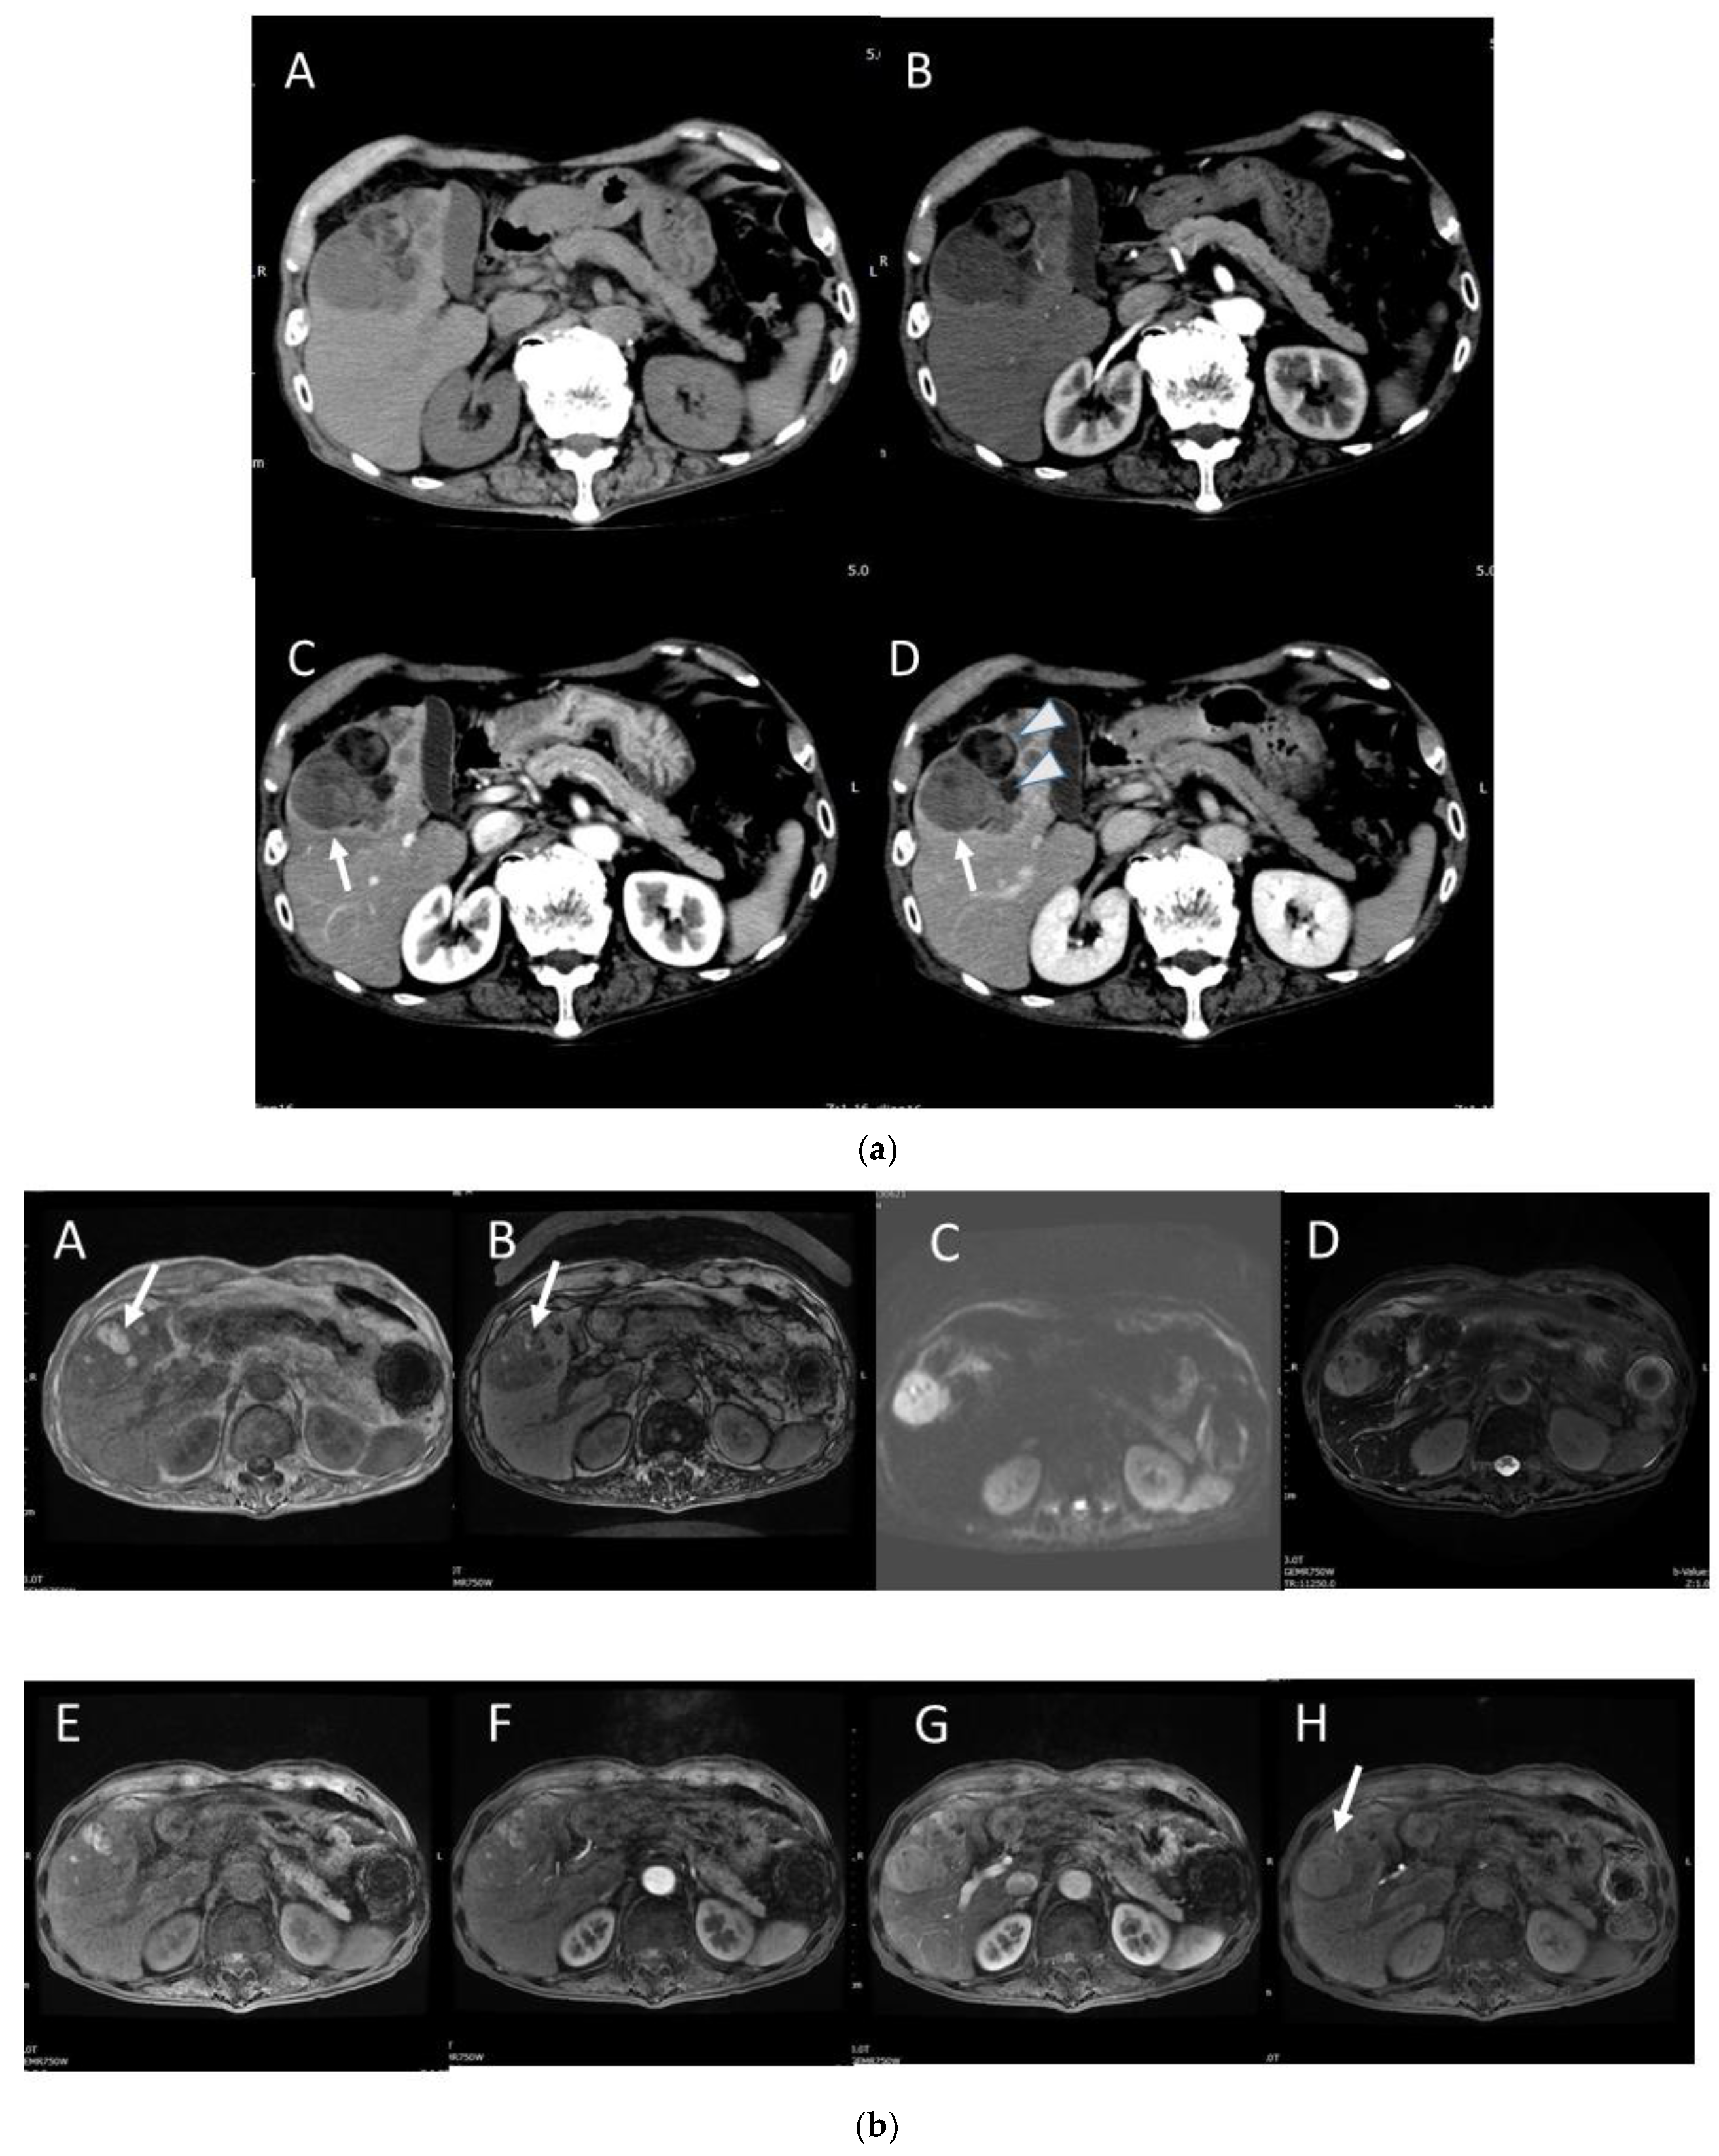

4.4. Moderately Differentiated Hepatocellular Carcinoma (Moderately HCC)

4.5. Poorly Differentiated Hepatocellular Carcinoma (Poorly HCC)